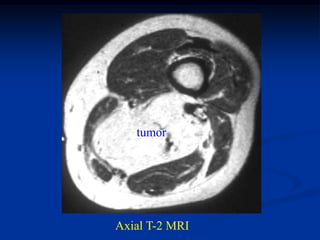

CLASSIC

Case #292

14 year female

hemangioma foot

AP x-ray showing

phleboliths

Lateral x-ray showing more phleboliths

tumor

Axial T-1 MRI

Axial T-2 MRI

Gross specimen with hemorrhagic cysts

Photomic

CLASSIC Case #292 14 year female hemangioma foot

• 270.

• 271.

Lateral x-ray showingmore phleboliths

• 272.

• 273.

• 274.

Gross specimen withhemorrhagic cysts